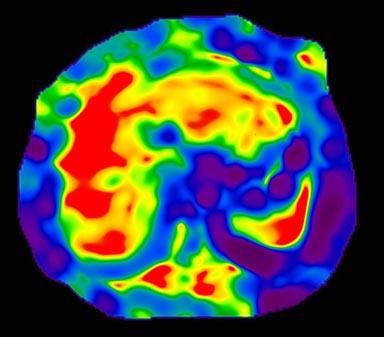

Figure 7. Color Elastogram, no mask, scale 0-20K

Figure 8. Color Elastogram, with mask, scale 0-20K